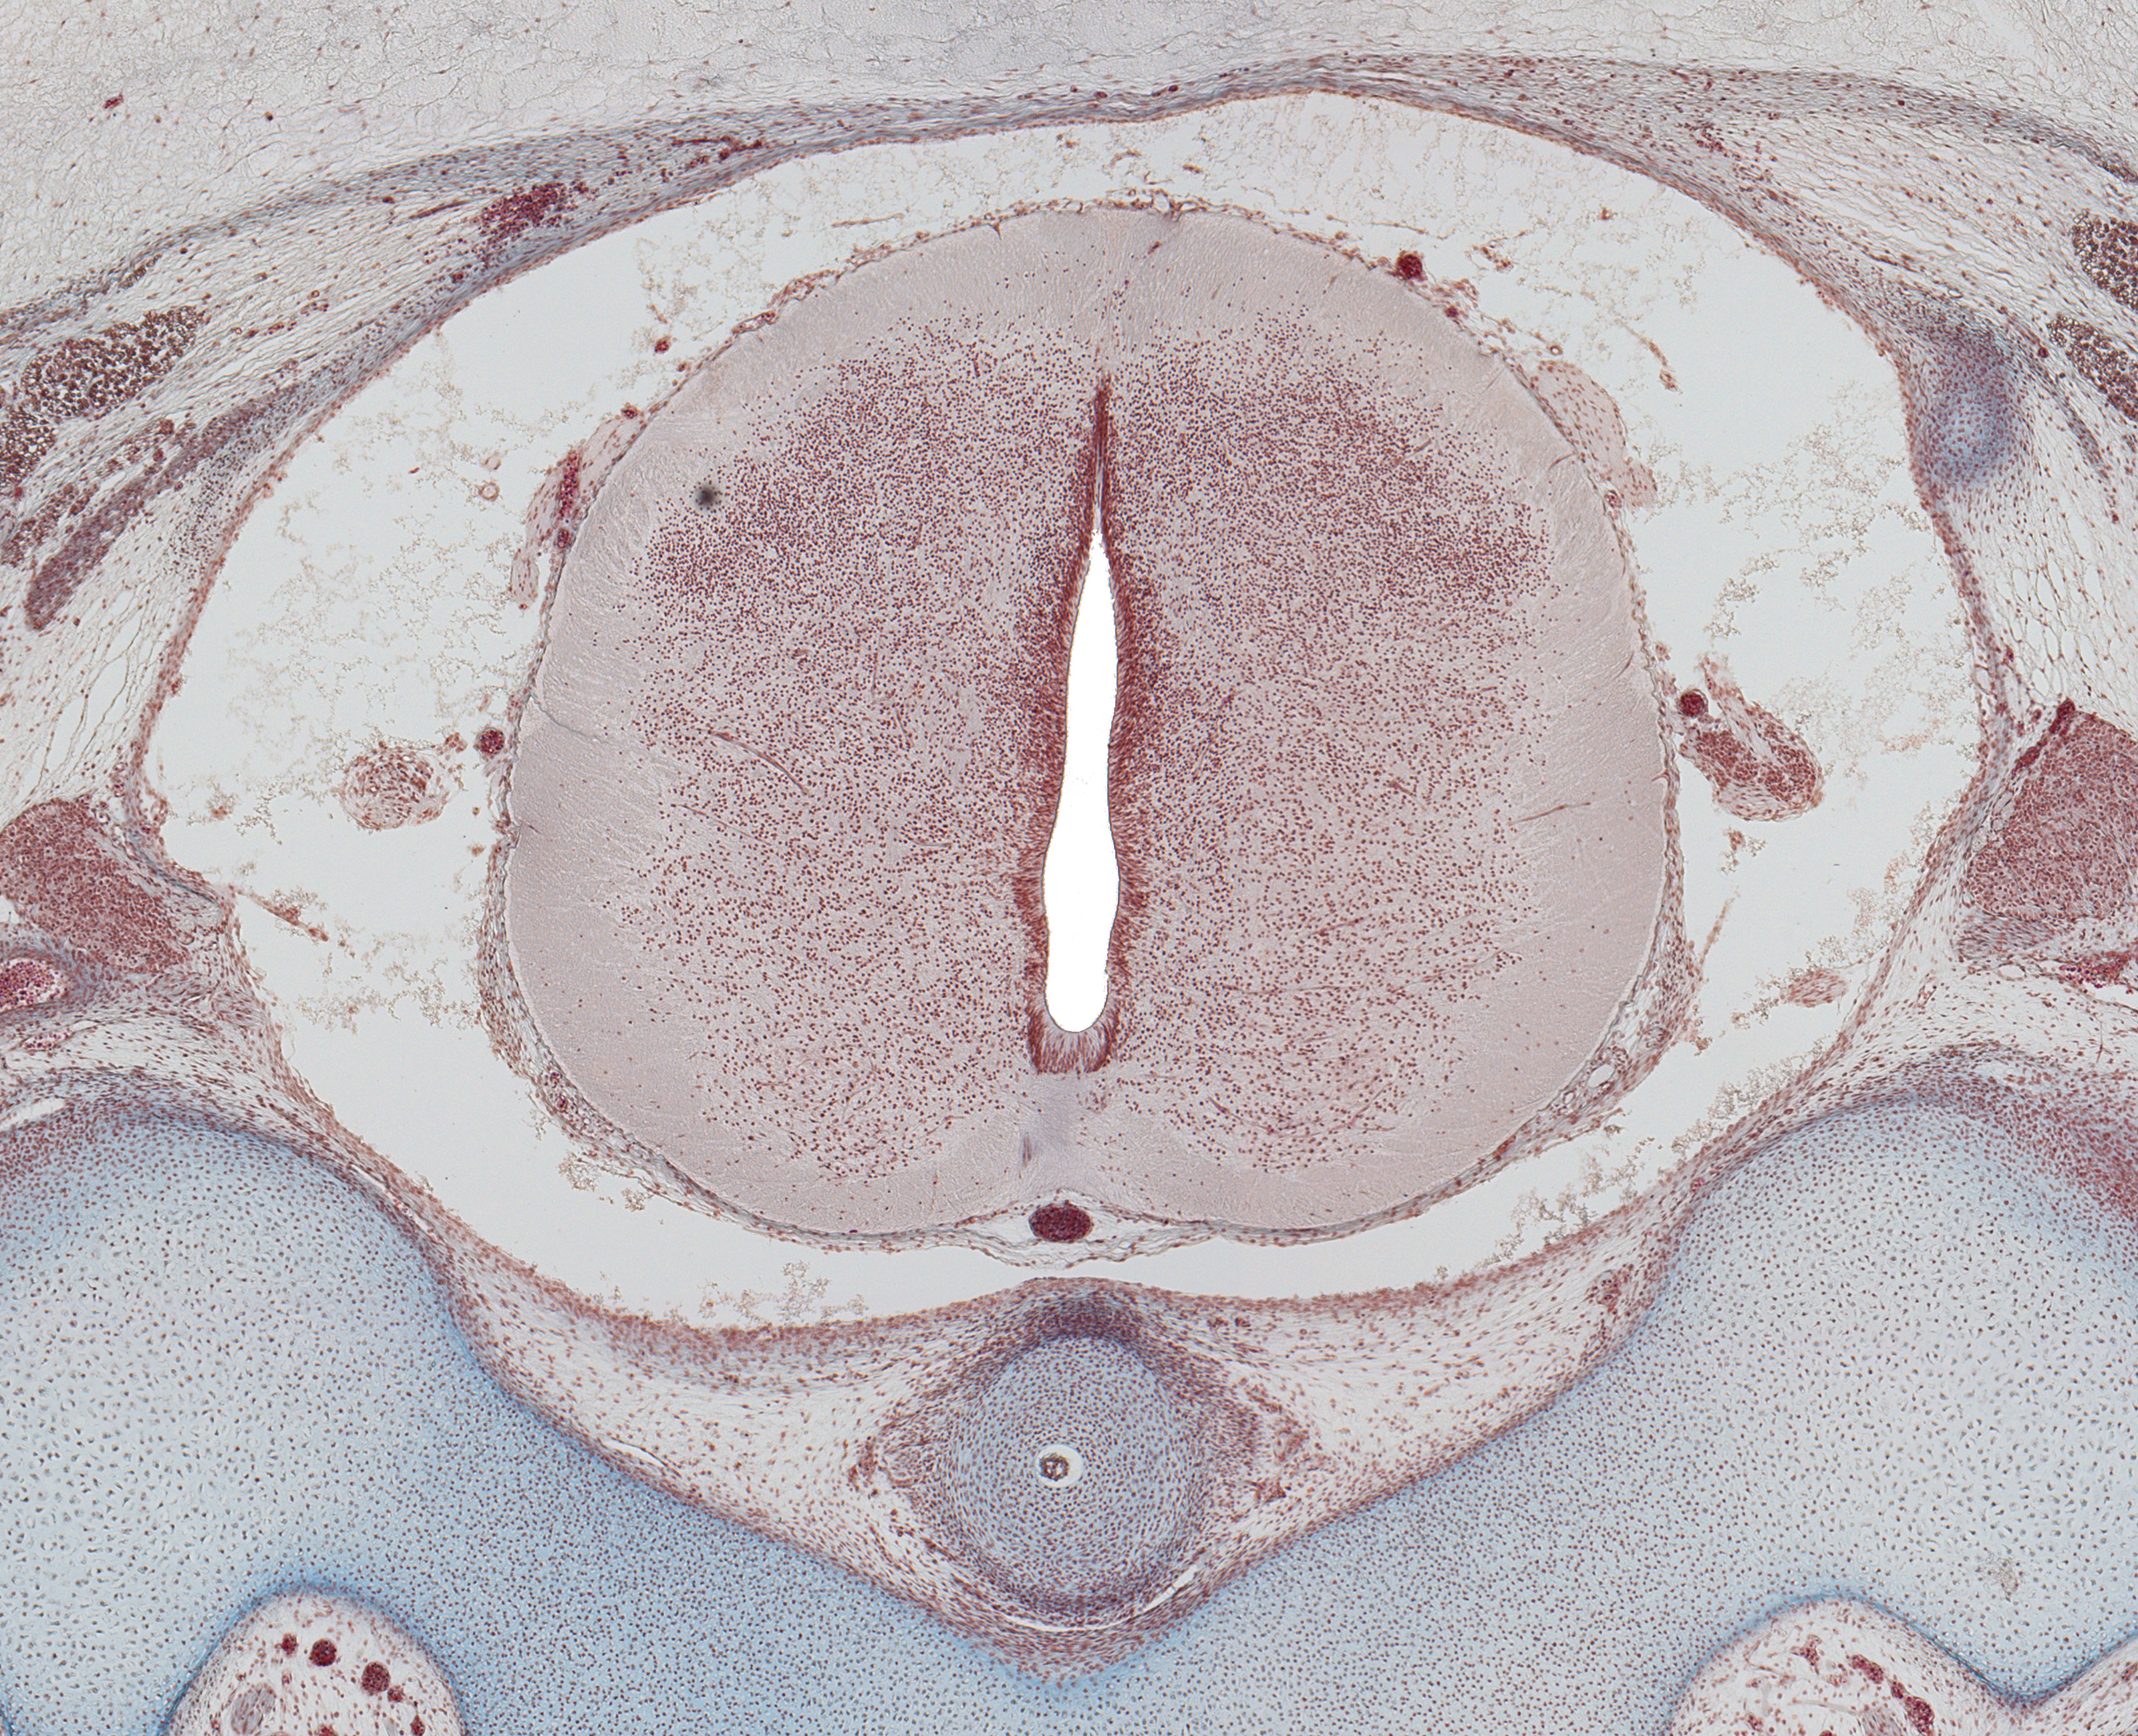

Tissue

–

Spinal Cord at C-1

Carnegie Embryo #9226

Location:

60-01-01